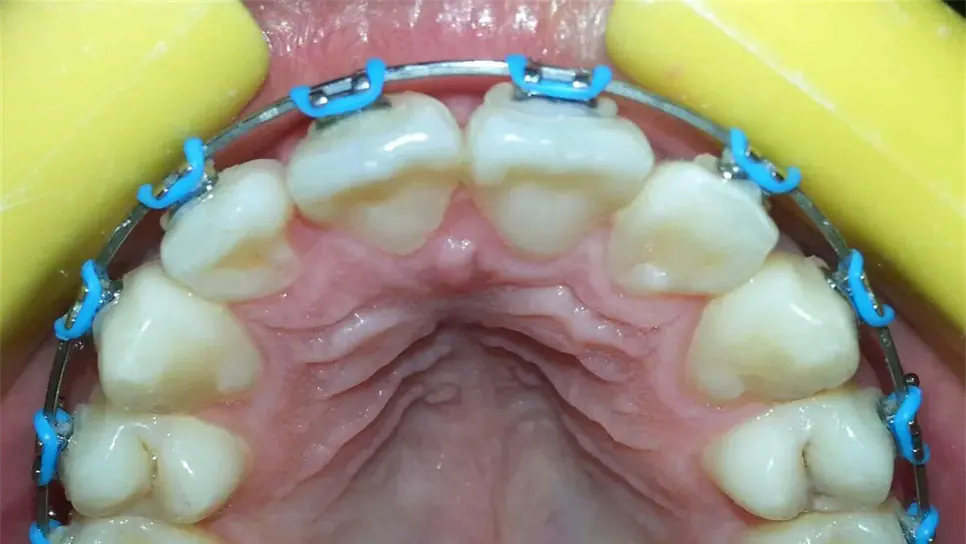

Un mal tratamiento de brackets puede llevar a provocar la pérdida de piezas dentales e incluso cambios en la estructura ósea del rostro.

Incluso señaló que un mal tratamiento de brackets puede llevar a provocar la pérdida de piezas dentales e incluso cambios en la estructura ósea del rostro.

Mencionó que es regular recibir pacientes que se dicen cansados de no notar cambios con sus antiguos médicos y al momento de revisar lo primero que se encuentra es con piezas de adorno que en ocasiones pueden llegar a ser piezas de brackets piratas.

"Cuando yo comienzo a consultar a pacientes que vienen de esos lugares me dicen que están cansados de no ver cambios, al momento de revisar me doy cuenta que faltan brackets, los que dicen brackets por 700 pesos, muchos van a cursos ya aprenden lo básico que es poner un bracket, pero para esto no tienen los conocimientos de ortodoncia, entonces el bracket no es mágico, quien hace el trabajo es el ortodoncista”, explicó.